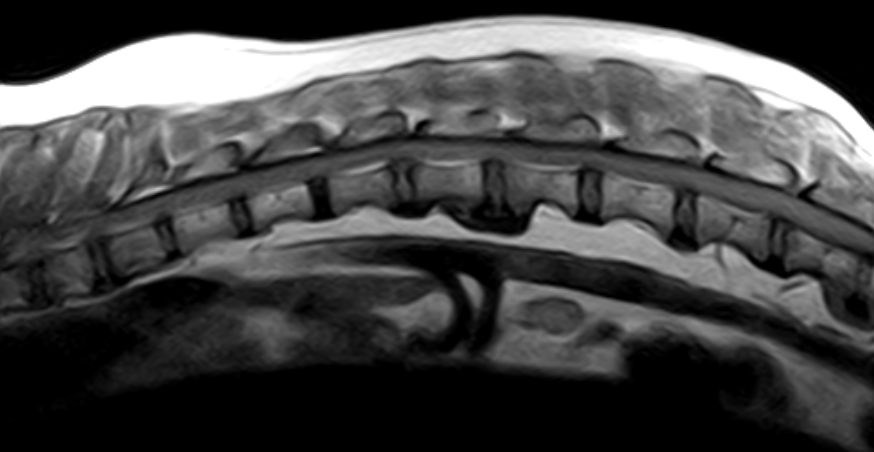

¿Como solicitar los segmentos de columna?

SEGMENTOS RESONANCIA DE COLUMNA PARTES DE LA COLUMNA

CERVICAL CERVICAL 1 - CERVICAL 7

CERVICOBRAQUIAL CERVICAL 6 - TORACICA 2

TORACICO TORACICA 4 - TORACICA 13

TORACOLUMBAR TORACICA 10 - LUMBAR 3

LUMBAR LUMBAR 1 - LUMBAR 7

LUMBOSACRO LUMBAR 4 - SACRO Y PRIMERAS COCCIGEAS